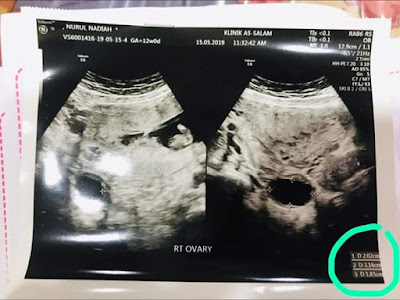

Checkup 12 weeks, cyst makin membesar lagi 1 cm. Hati dah tak keruan. Tapi doktor kata masih ok lagi. As long as bawah 5 cm.

| Hamil 12 minggu, Cyst Makin Membesar |